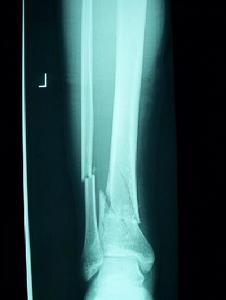

(2)根據具體情況選擇內固定器材,如適當規格和大小的鋼板、螺釘及髓內釘等。在同一創口內只許用同種金屬製造的內固定器材,以免發生電解作用,影響骨折癒合。

(3)術中再次觀測內固定物與骨折端的解剖特點是否適應,如髓內釘的直徑和髓腔是否一致。

(4)內固定物欠牢固者,術後應輔以確實外固定直至臨床癒合,內固定物牢固者術後可根據情況決定是否以石膏托保護。髖部內固定後可輔以皮牽引或穿木板鞋,以防患肢外鏇。

(2)定期X線拍片觀察內固定物的位置及骨折癒合情況。內固定物有滑出、變位者應設法糾正,癒合延遲者應予以確實外固定。